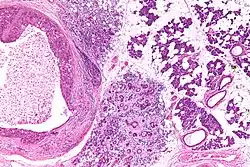

| Low magnification micrograph of a salivary duct carcinoma with characteristic comedonecrosis (left of image) adjacent to normal parotid gland (right of image). H&E stain. | |

Their histologic appearance is similar to ductal breast carcinoma.

Very low mag.

Intermed. mag.

Very high mag.